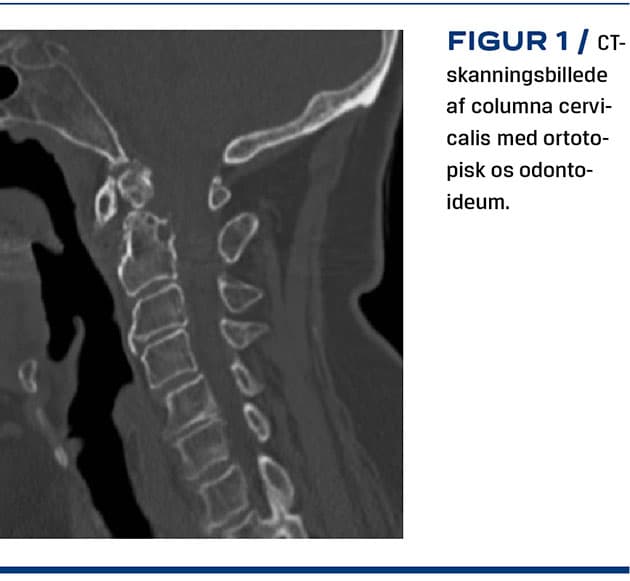

OO defineres som et mindre knoglefragment, der er separeret fra basis af en forkortet dens uden ossøs kontakt [4], og kategoriseres på grundlag af den anatomiske placering enten ortotopisk, hvor knoglefragmentet er normalt placeret i forlængelse af dens med funktionel kontakt til arcus anterior af atlas (C1) (Figur 1) eller dystopisk med funktionel kontakt til basis af os occipitale anteriort for foramen magnum [5]. Basis af C2 og den forkortede dens kan have forskelligt udseende og beskrives som enten rund-, kegle- eller stumpformet, hvor førstnævnte er associeret med flest gener [6].